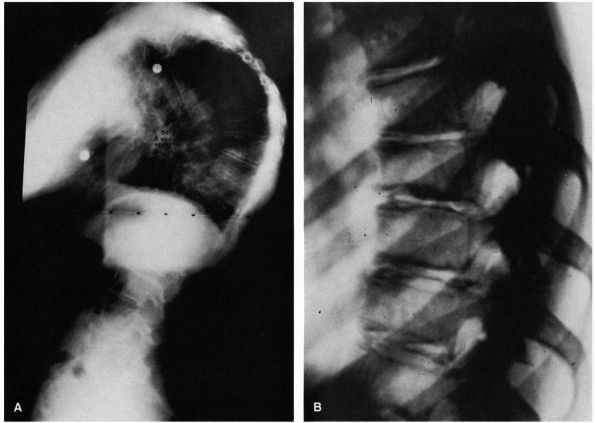

FIGURE 16-21. (A) Standing lateral radiograph of patient with Scheuermann disease (94°). Note the marked vertebral wedging at the curve apex. (B)

Coned-down views of spine in another patient with Scheuermann disease. Note the vertebral wedging, endplate irregularity, and disc space narrowing. |

standing lateral radiograph of the spine. Standard radiographic

technique is important. The radiograph should be taken with the arms

parallel to the floor and resting on a support (Figure 16-21).

An alternative method is to curl the fingers and to put the pip finger

joints in the supraclavicular notch on each side. It is important to

see the entire spine to measure the thoracic kyphosis, lumbar lordosis,

and any secondary cervicothoracic curves that may accompany the

kyphosis. The kyphosis is measured by determining the angle between the

maximally tilted end vertebrae (similar to the Cobb method for

measuring scoliosis). A PA scoliosis film should be obtained to detect

the presence and magnitude of any associated scoliosis.